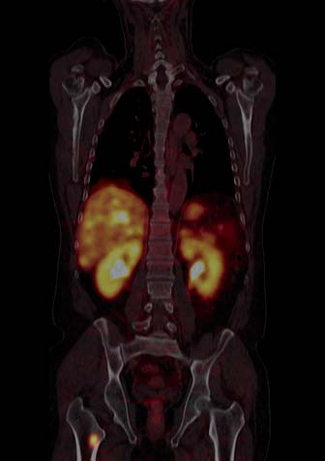

Tumor mesenquimal fosfatúrico

La osteomalacia oncogénica es un síndrome paraneoplásico caracterizado por dolor óseo y muscular, pérdida de densidad mineral ósea, marcada disminución del nivel plasmático de 1,25 dihidroxicolecalciferol, hipofosfatemia e hiperfosfaturia (Figura 13). La causa puede ser un tumor mesenquimal oculto que secreta una hormona llamada factor de crecimiento fibroblástico-23 (FGF-23), que pertenece a una clase de factores u hormonas conocidos como fosfatoninas41,42. Puede darse también en asociación con otras enfermedades tales como: cáncer de próstata, cáncer de células pequeñas, neurofibromatosis, cánceres hematológicos, síndrome del nevus epidérmico y displasia fibrosa poliostótica. El tumor mesenquimal, desde el punto de vista histológico, puede ser parecido a un variado número de neoplasias muchas de ellas benignas (hemangiopericitomas, hemangiomas, sarcomas, fibromas osificantes, granulomas, tumores de células gigantes y osteoblastomas)43. La resección quirúrgica del tumor es generalmente curativa. Sin embargo, muchos de estos tumores son pequeños y de ubicación inusual por lo que su localización suele ser muy difícil. Pueden aparecer en huesos o tejidos blandos, en cualquier parte del cuerpo. PET/CT con F18-FDG es el método más sensible para su localización, sin embargo, de baja especificidad debido a la captación de F18FDG por lesiones no neoplásicas tales como reparación de fracturas óseas, que son muy frecuentes en estos pacientes. Debido a que numerosos tumores mesenquimales expresan receptores de somatostatina, tales como tumores óseos, vasculares y perivasculares (osteosarcomas, tumor de células gigantes, angiosarcomas, hemangiopericitomas), sarcomas sinoviales, histiocitomas y tumores de origen muscular (leiomiomas, leiomiosarcomas y rabdomiosarcomas)44, el uso de trazadores para receptores de somatostatina es útil en estos pacientes. Tanto el SPECT con In111-pentatreotide como el PET con Ga68-DOTATATE u otros análogos han sido usados exitosamente para localizar estos tumores (Figura 14). La adición de imágenes estructurales (SPECT/CT y PET/CT) mejoran aún más el rendimiento del examen. Particularmente en estos casos es necesario realizar un examen de cuerpo total, desde el vértex craneal hasta los pies, incluyendo las extremidades superiores completas, debido a que el tumor puede estar en cualquier parte. Por el momento no hay estudios que comparen el rendimiento del In111-Octreoscan con PET con Ga68-octreotide.